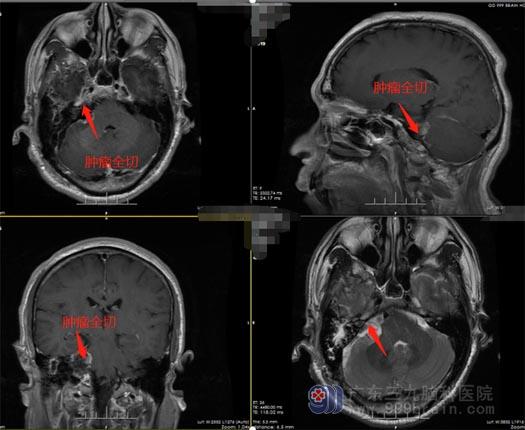

广东三九脑科医院鲁明副院长、神经外五科王国良主任高度重视钟先生的病情,反复讨论后一致同意手术治疗,而手术治疗的难点在于:手术既要切除肿瘤,又要保住患者的神经功能。患者听神经、面神经位于肿瘤的前下方,不仅位置很深,且周围结构复杂,在如此狭小的空间里,要想取出肿瘤,难度和风险可想而知。稍有差池,便会损伤颅神经、脑血管。很快,神经外五科团队为钟先生实施了右侧听神经瘤切除术。术中,医生从患者后侧行8厘米切口,见肿瘤位于右侧桥小脑角,予显微镜下全切肿瘤。术后钟先生神志清醒,因术中各组颅神经保护良好,钟先生无明显颅神经损伤的阳性体征表现,恢复良好。

▲术后